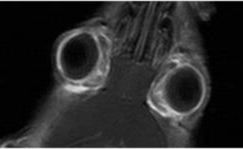

- マウスの涙が眼球を覆っている様子

左:マウスの画像 中央:涙を強調した画像 右:通常の画像

中央の画像では、マウスの眼球のまわりにある涙を観察できます。 -